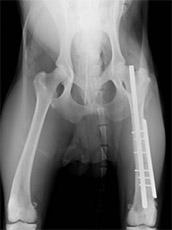

後足大腿骨骨折

このタイプはそう簡単に骨折する場所ではありませんが、いちど骨折すると筋肉が一番多い場所なので、整復手術するのに手間がかかります。

手術前

手術後

ラブラドールの交通事故による左大腿骨骨折です。体重も重く、動きも激しい犬種なので、かなり強固な固定が必要でした。髄内ピン+プレート固定により治療を行いました。